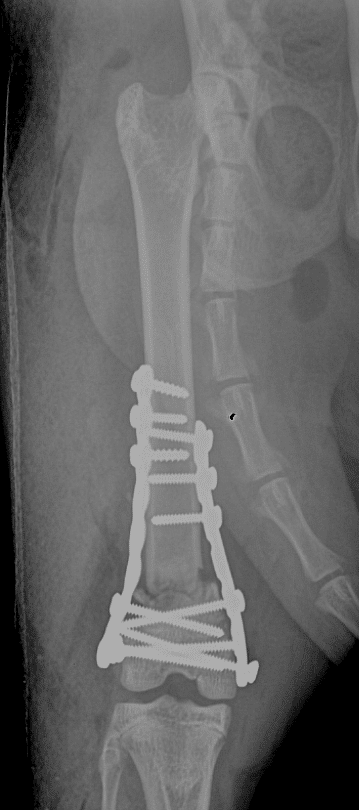

Les fractures chez le chat